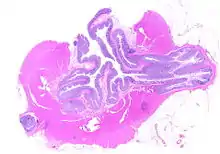

Segmental colitis associated with diverticulosis (SCAD) is a condition characterized by localized inflammation of the colon between diverticula (interdiverticular mucosa) while sparing the diverticular orifices. SCAD may lead to abdominal pain, especially in the left lower quadrant, intermittent rectal bleeding, and chronic diarrhea.

Pathophysiology

The precise mechanisms by which diverticula are formed are unknown.[1] Multiple theories have been proposed including genetic susceptibility, diet, intestinal motility, changes in the microbiome, and inflammation. One leading theory suggests that diverticula form in weakened areas of the colon wall that are subjected to increased pressure.[1] The strength of the colon wall is known to decrease with age.[1] Previous theories proposed that impacted fecal matter and certain foods would get stuck in diverticula (thereby causing trauma), which caused poor blood flow, death of the affected intestinal wall cells, and intestinal perforation.[1] Newer theories have called this paradigm into question.[1]